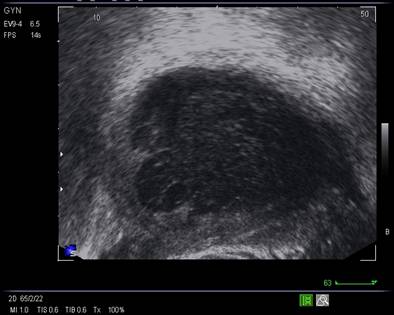

Fig. nr.374. Ovar in cadrul unui sindrom de ovar polichistic , cu multiplii foliculi (peste 7- 10 pentru fiecare sectiune ) dispersati in intreaga masa ovariana, de talie mica sub 5- 6 mm diametrul folicular

Fig. nr.375. Sindrom de ovar polichistic sub tratament cu methformin, se remarca la nivelul ovarului stang multiplii foliculi de talie mica dispusi periferic.